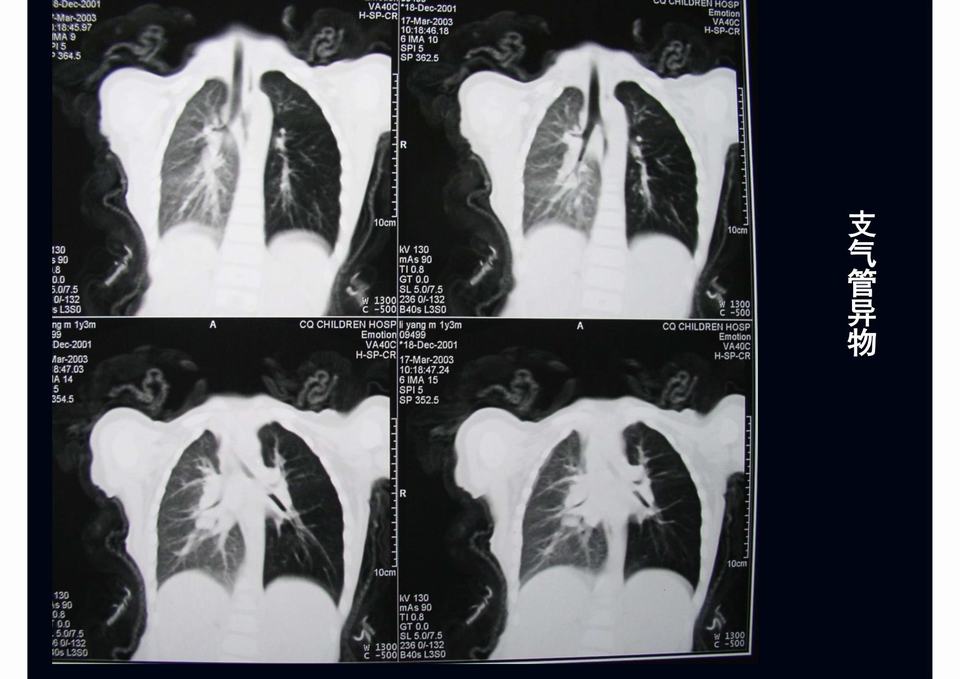

图02